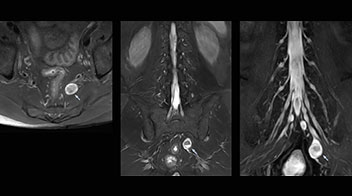

At Northern Fukushima Medical Center in Japan, excellent MRI visualization of nerves helps support confident diagnoses and informs surgical treatment decisions for patients with lower limb symptoms. MRI technologist Tanji and orthopedic surgeon Dr. Yabuki share how direct nerve visualization with the 3D NerveVIEW method adds information when diagnosing atypical herniations. The additional insights changed their way of working and benefit their patient care, as illustrated by some clinical examples.

“In patients with lower extremity neurological symptoms, NerveVIEW helps us to determine the disease matching the patient’s symptoms by directly visualizing the nerves. We use the sequence mainly, when there is suspicion of intraforaminal stenosis, extraforaminal stenosis or lateral disc herniation, which is often based on routine T2- and T1-weighted images. Additionally, the excellent depiction of the course of nerves makes NerveVIEW a good navigator when applying treatment such as block therapy or surgery.”

“Although symptoms of typical disc herniation and atypical hernia are very similar, the actual site of herniation is different. It is therefore important to characterize the nerve’s condition both inside and outside of the intervertebral foramina. “Conversely, if we see no abnormality in NerveVIEW, we can assume at least that there is no severe condition that requires surgery. Like this, it can help us avoid unnecessary surgery. NerveVIEW can have a tremendous impact in this way.”

“NerveVIEW is really useful for those cases where a nerve disorder is strongly suspected based on the clinical examination but our regular MRI images do not show any findings. These atypical herniations and spinal canal stenosis, occurring in 5% to 15% of the total lumbar herniation/stenosis cases are our main target when using NerveVIEW,” says Dr. Yabuki.